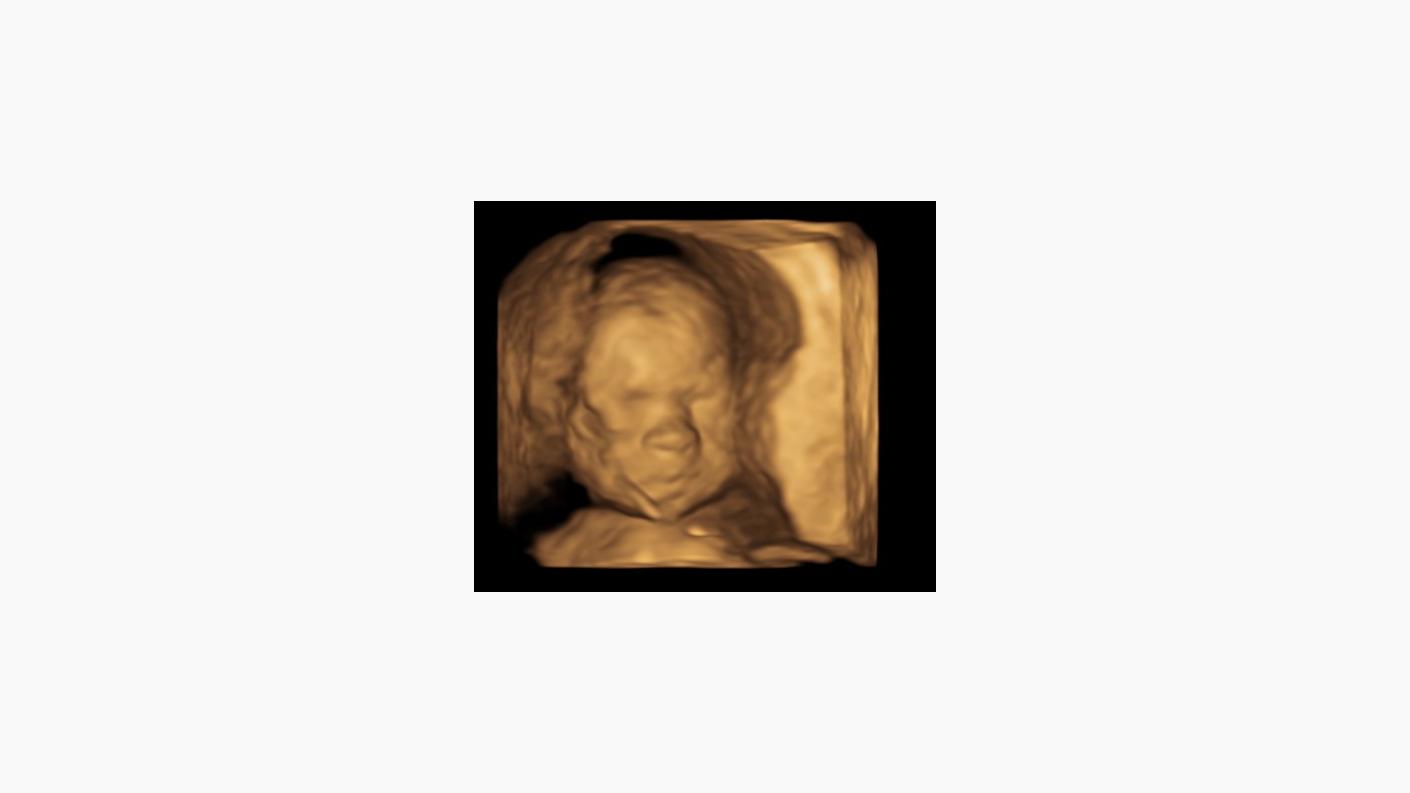

Cu ajutorul unui ecograf nou, Voluson 3D și 4D, acum se pot face noi evaluări, fiind posibilă vizualizarea cu acuratețe a detaliilor de anatomie fetală. Cel mai important examen morfologic este recomandat a fi efectuat între săptămânile 21 și 24 de sarcină.